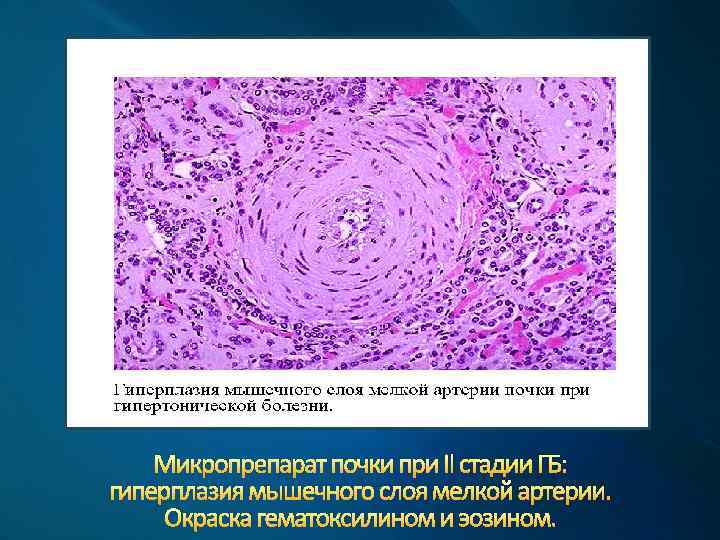

Микропрепарат почки при II стадии ГБ: гиперплазия мышечного слоя мелкой артерии. Окраска гематоксилином и эозином.